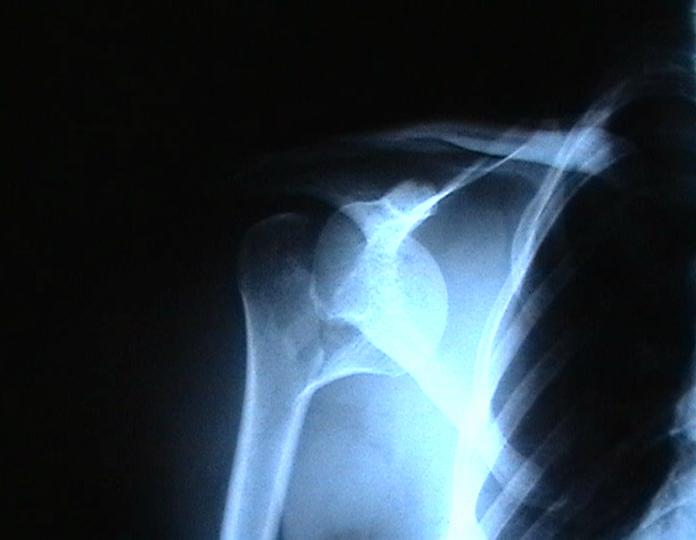

Согласен с вашим мнением -асептический некроз головки плеча. Есть ли у вас надежды на реваскуляризацию головки ? Если надеетесь, то имеет смысл продолжать физио, если нет, то следует думать опротезировании.

Переломовывих плеча сложная проблема и технически не уверен как для коллег, но для меня сколько я не встречался, технически сложно *вытянуть* вывихнутую головку из-под впадины. Последнее время не применяю пластины для фиксации перелома, а использую спицы и проволочную петлю (тем более часто и густо спонгиозные винты не держатся в головке прочно).